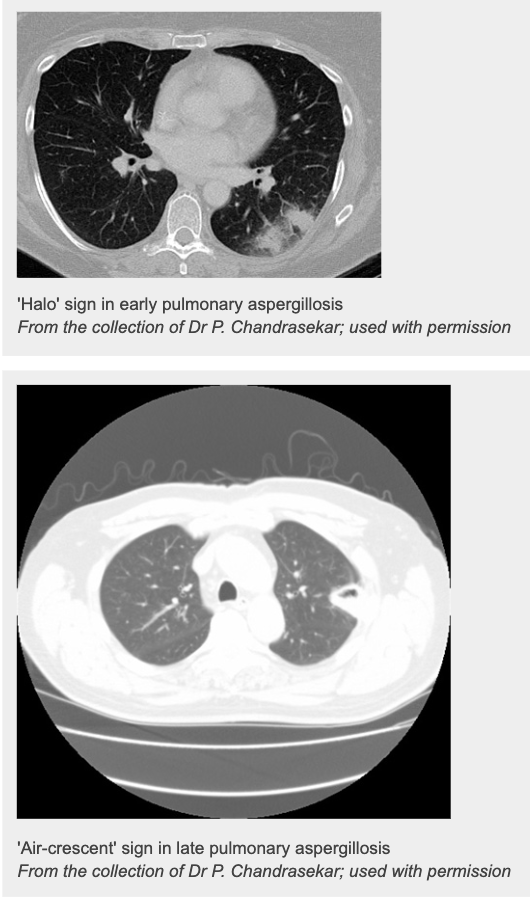

What is Invasive aspergillosis (IA)?

What are some primary investigations for ?Invasive Aspergillosis